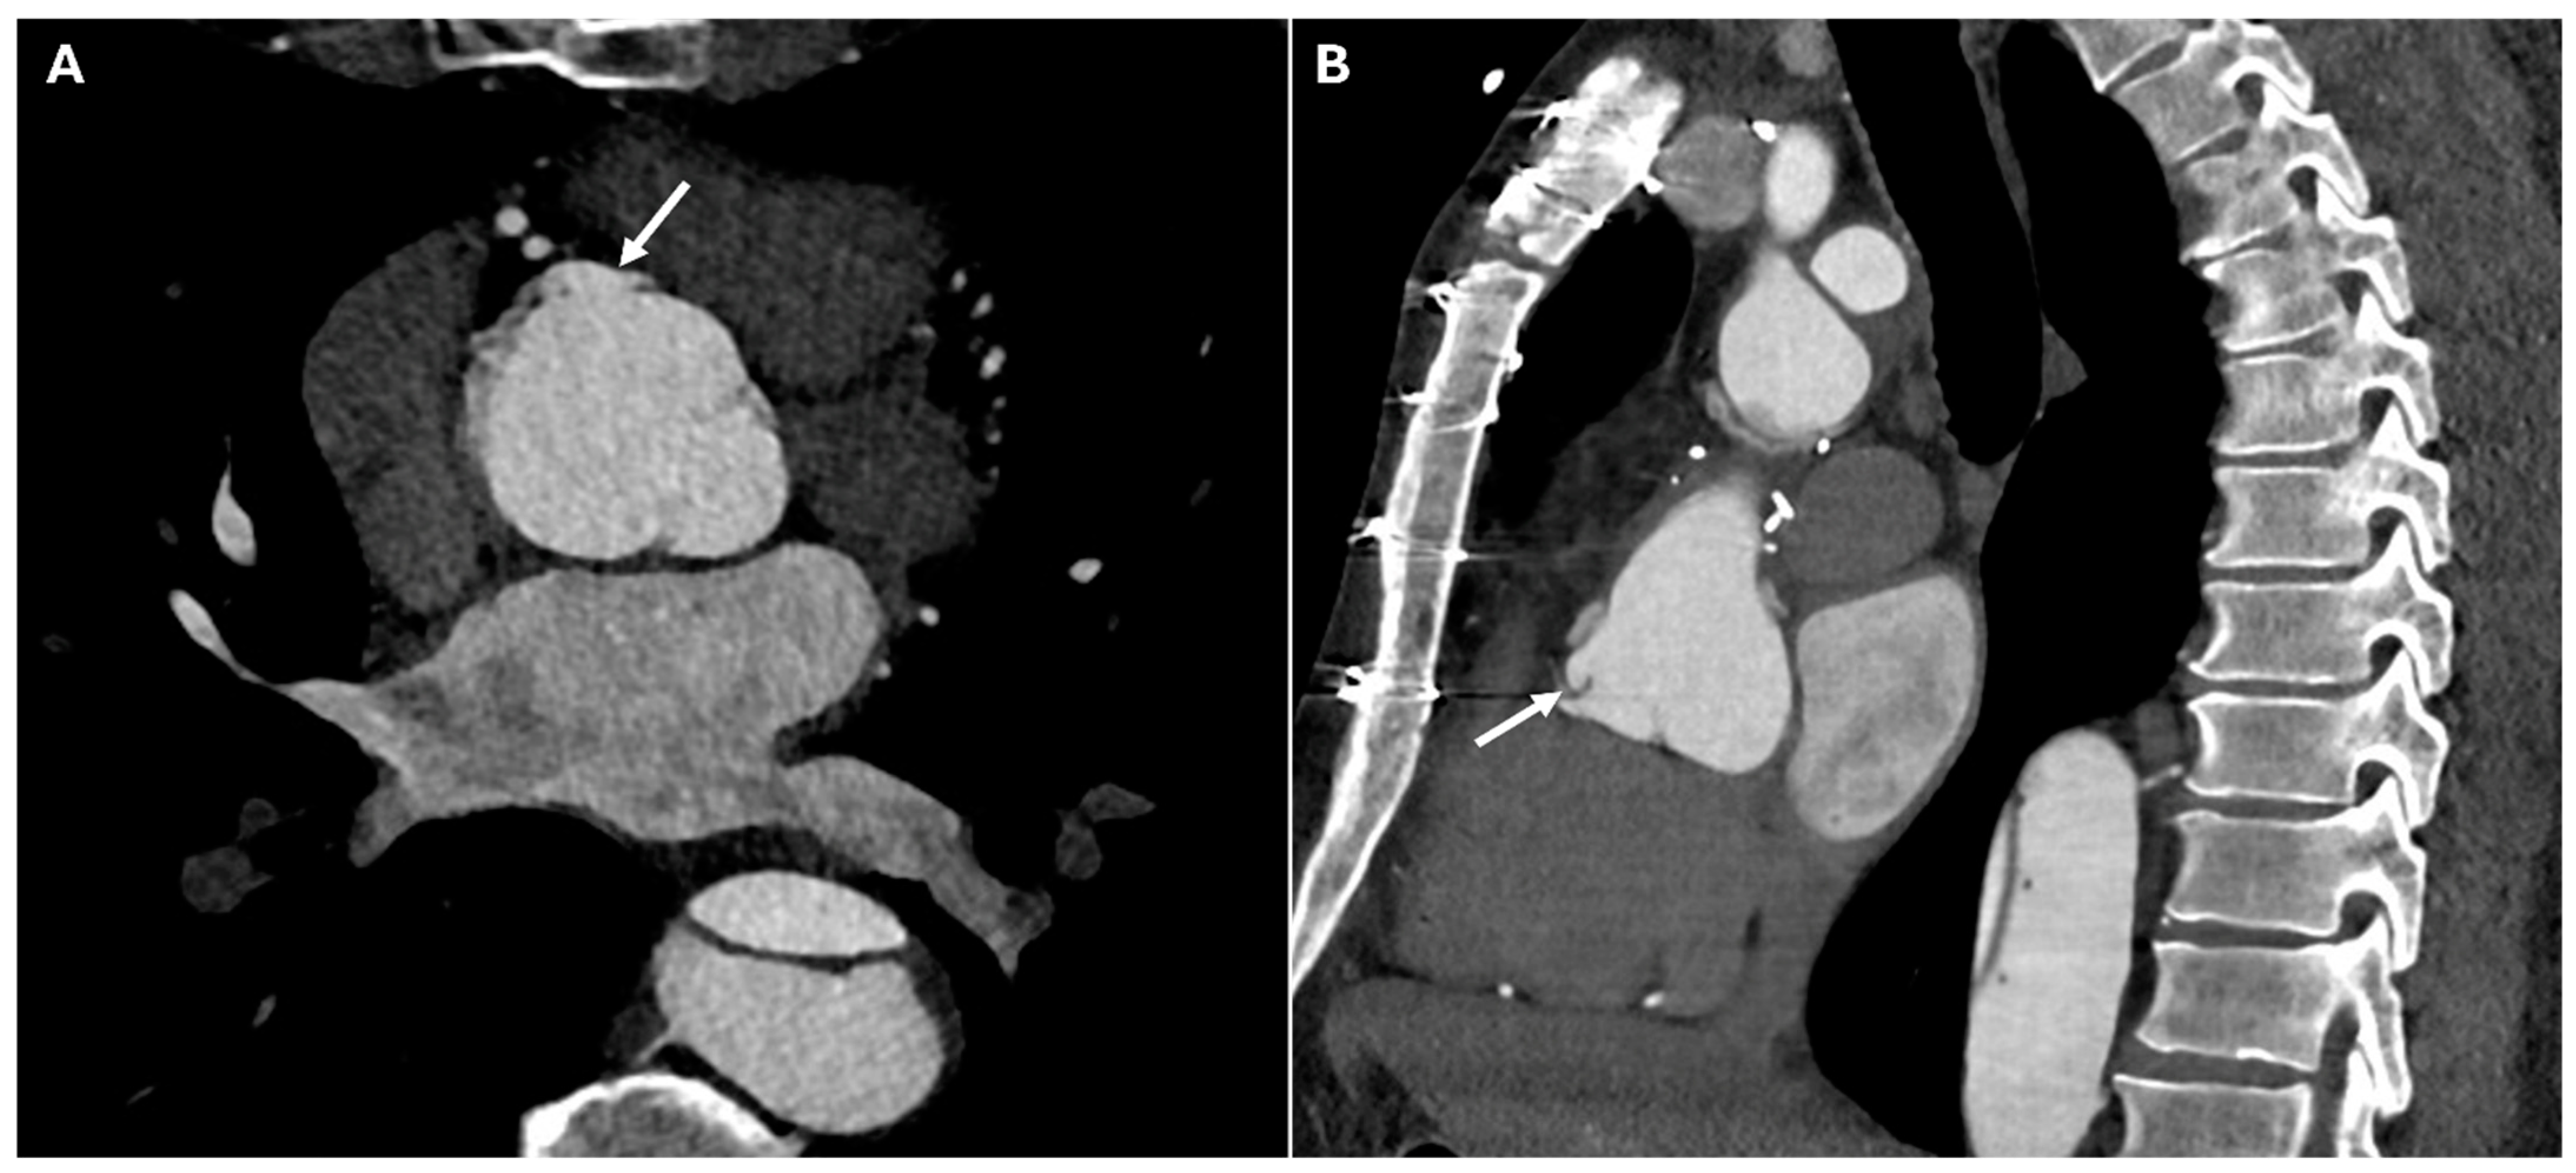

| Pseudoaneurysm | Suture failure, infection, chronic mechanical stress | Contrast-filled sac adjacent to graft, narrow neck | High rupture risk |

| Perigraft Fluid Collection and Infection | Post-surgical infection | Rim-enhancing fluid collections, intrinsic air | Can progress to graft infection and sepsis |

| Pericardial Effusion and Tamponade | Post-surgical tamponade | Fluid collection in pericardial sac, cardiac chamber compression, septal bowing | May impair cardiac function |

| Endoleaks (TEVAR) | Incomplete sealing, graft migration | Persistent contrast enhancement outside stent graft lumen | Can lead to aneurysm expansion and rupture |

| Perigraft fluid | Thin, homogeneous, no enhancement | Heterogeneous, rim-enhancing, septated |

| Graft folds | Linear, symmetric, stable on serial CTA | New, irregular, or associated with contrast leak |

| Anastomotic bulge | Small, smooth, uniform | Saccular, eccentric, narrow-necked (suggests pseudoaneurysm) |